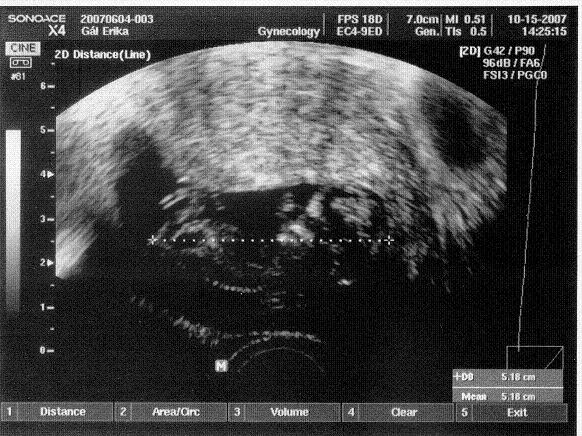

Zsuzsófi, de jó, hogy ezt az uh képet föltetted! Tényleg nem olyan sok részlet látszik, de olyan jó elképzelni, hogy már ekkora!